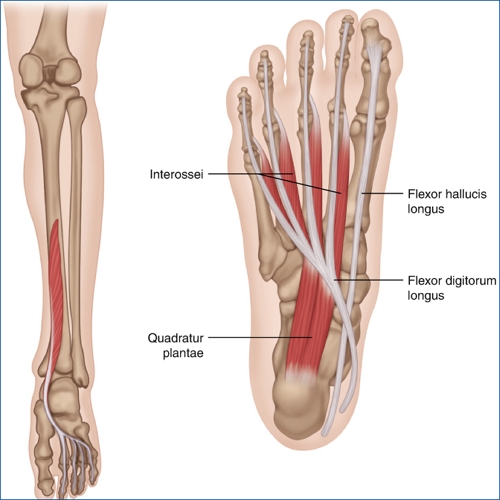

4. 발가락 굴곡근 힘줄염(Flexor Tendonitis)

발가락을 구부리는 근육의 힘줄에 발생하는 염증으로, 발바닥 앞쪽에서 통증을 유발합니다. 반복적인 활동이나 부적절한 신발 착용으로 인해 발생할 수 있습니다.